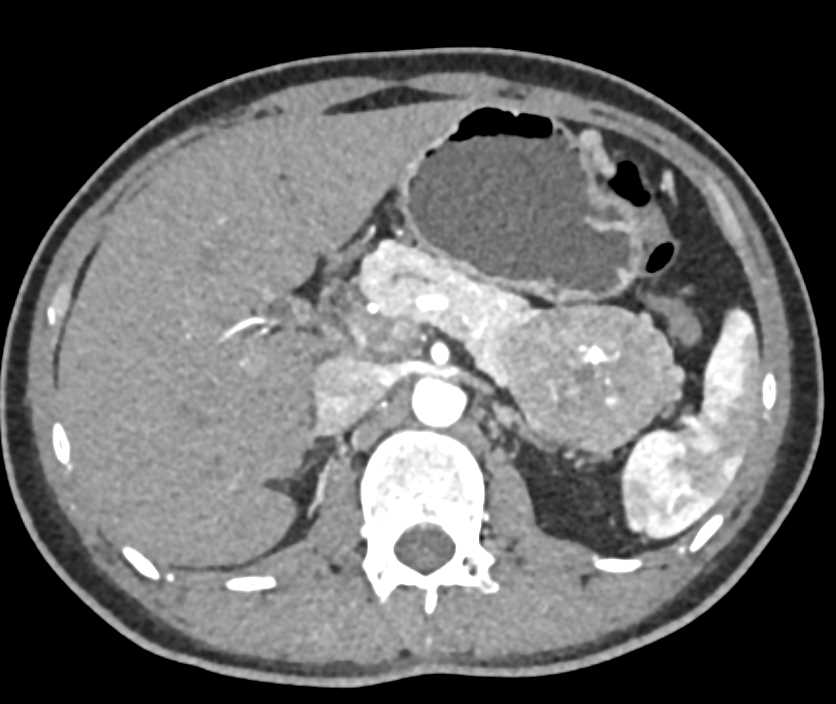

PNET Tail of the Pancreas